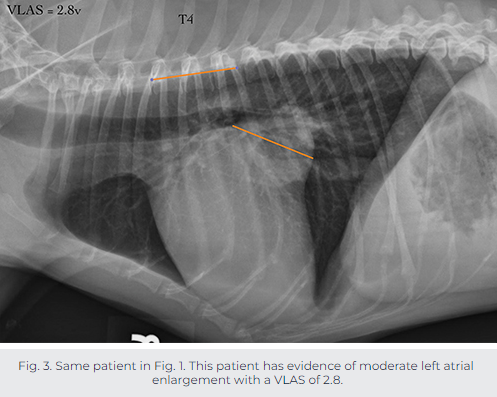

모식도에서 처럼 기관분지부의 아래중심부 끝점에서 대정맥과 심장이 겹쳐지는 부분까지의 거리를 측정하는 방법으로 측정된 길이와 흉추 4번부터 흉추체의 길이를 비교하는 측정방법이다.

cut off는 2.3으로 이보다 크면 심비대를 의미한다.

| 개의 VLAS 정상범위 : 1.8~2.3 |

실측정 예시는 다음과 같다.